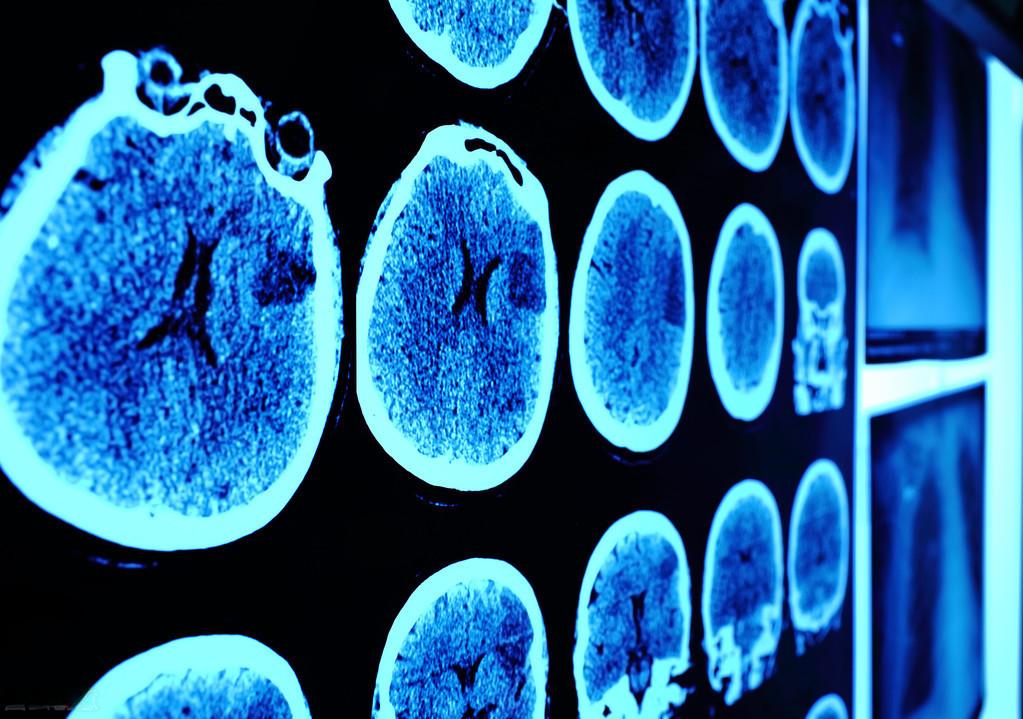

腔隙性脑梗死是一种特殊的脑血管疾病 ,其特点是梗死面积小,通常直径在2-15毫米之间。这种疾病在中老年人群中发病率较高,60-70岁人群中接近50%有腔隙性脑梗死,70-75岁人群中这一比例可达50-70%,80岁以上人群则绝大多数有多发性腔隙性脑梗死。